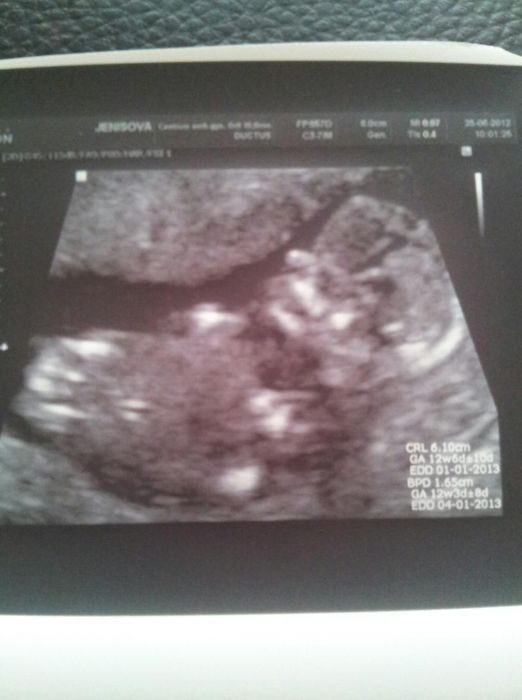

Já dnes v Č.B v Centru lékařské genetiky absolvovala odběr plodové vody (dle krve ze screeningu hrozil Down). Nejprve nám (byly jsme tam tři maminy)  pan doktor Čutka st. dal malou přednášku, co a jak nás čeká . Je trošku svérázný člověk, ale my s přítelem už jsme měli tu čest začátkem roku, takže nás to nepřekvapilo ani nerozhodilo. Po krátkém čekání udělali můj první UZ přes břicho - dělal ho MUDr. Čutka ml. a vše vysvětlil, ukázal, změřil a řekl, co to bude a že je mimi zdravé. Ani fotečka nechyběla. Pak jsme chviličku čekali na chodbě a hurá na oděr. Převléct do anděla a na stůl. Tam byli MUDr. Schacherl a paní MUDr. Šustrová. Vpich byl tak rychlý, že to jen maličko štíplo a pak už jsem radši ani nedýchala, aby se něco nepokazilo. Pak mi píchli injekci proti krvácení - na UZ bylo vidět, jak do plodové vody maličko utíká krev, (což je prý stejné, jako po píchnutí do prstu), ale asi po 3-4min to zkontrolovali UZ znovu a vše bylo OK. Nakonec mi sestřička odebrala krev, prý ji porovnávají s tou plodovou vodu a mohli jsme jet domu. V autě mě maličko břicho bolelo, jakoby tlačilo, ale teď poctivě ležím a je to docela dobrý. Za pár dní mi prý zavolají předběžný výsledek a za cca 3 týdny mi pošlo výsledky poštou. Takže nezbývá, než čekat bezproblémový výsledek a být 3 dny hodná a ležet - což je nuda, ale vydržím. Pro mimi všechno! Wink  Takže holky,pokud některou z Vás taky čeká odběr - nebojte se, žádná hrůza to není...